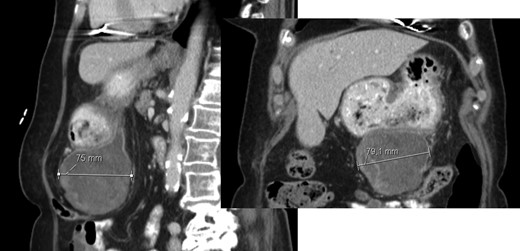

A 78-year-old woman with past medical history of hypertensive cardiopathy and bearer of a pacemaker, was referred to our Hepatobiliary Unit with diagnose of a liver mass discovered on CT scan, which was performed after complaints of nausea and postprandial infarction. CT scan (Fig. 3) showed a voluminous heterogeneous, lobed mass, displaying heterogeneous uptake contrast, relatively vascularized, localized in segment 1, with exophytic growth to the left lobe, with 18.5 × 13.8 × 15.6 cm; the tumor caused deviation of the stomach to the left.

AP-CT – voluminous heterogeneous mass in segment 1 with 18.5 cm in diameter.

At 16 months, follow-up, local recurrence was identified on CT scan, showing an expansive heterogeneous lesion, below the stomach, with 7.4 cm of maximum diameter, showing no cleavage plan with the stomach (Fig. 4).

AP-CT – expansive heterogeneous lesion, with 7.4 cm, showing no cleavage plan with the stomach.